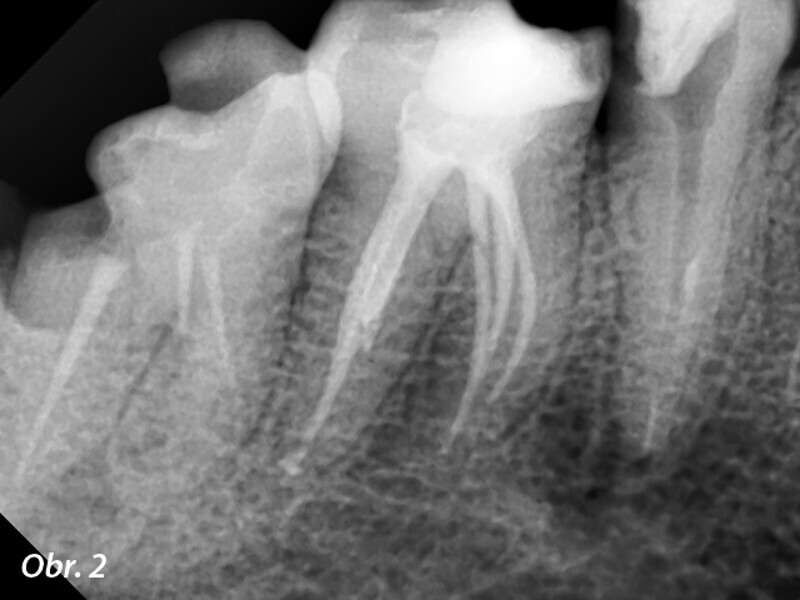

Endodontické ošetření s modulárním NiTi systémem